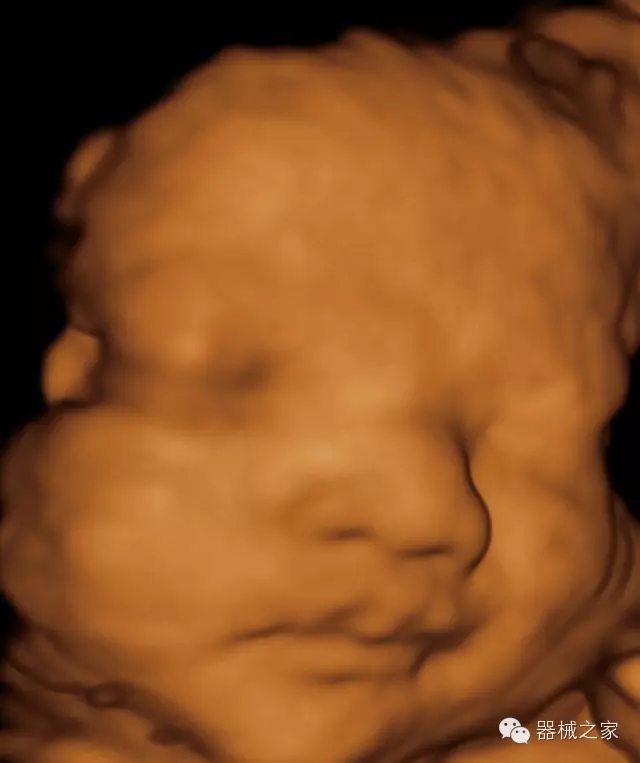

品牌:飛依諾(VINNO)

公司簡介:

飛依諾科技(蘇州)有限公司2010年在蘇州工業(yè)園區(qū)成立,公司致力于成為世界一流醫(yī)療超聲品牌。核心創(chuàng)始團(tuán)隊(duì)囊括了來自于全球著名公司十多位資深研發(fā)和市場人才,均為業(yè)界精英。

官方網(wǎng)站:www.vinno.com

經(jīng)典產(chǎn)品:VINNO 6

臨床圖片賞析

產(chǎn)品特點(diǎn)

·完整的3D/4D臨床應(yīng)用,STIC, MCUT 和Auto NT等滿足產(chǎn)科所有應(yīng)用;